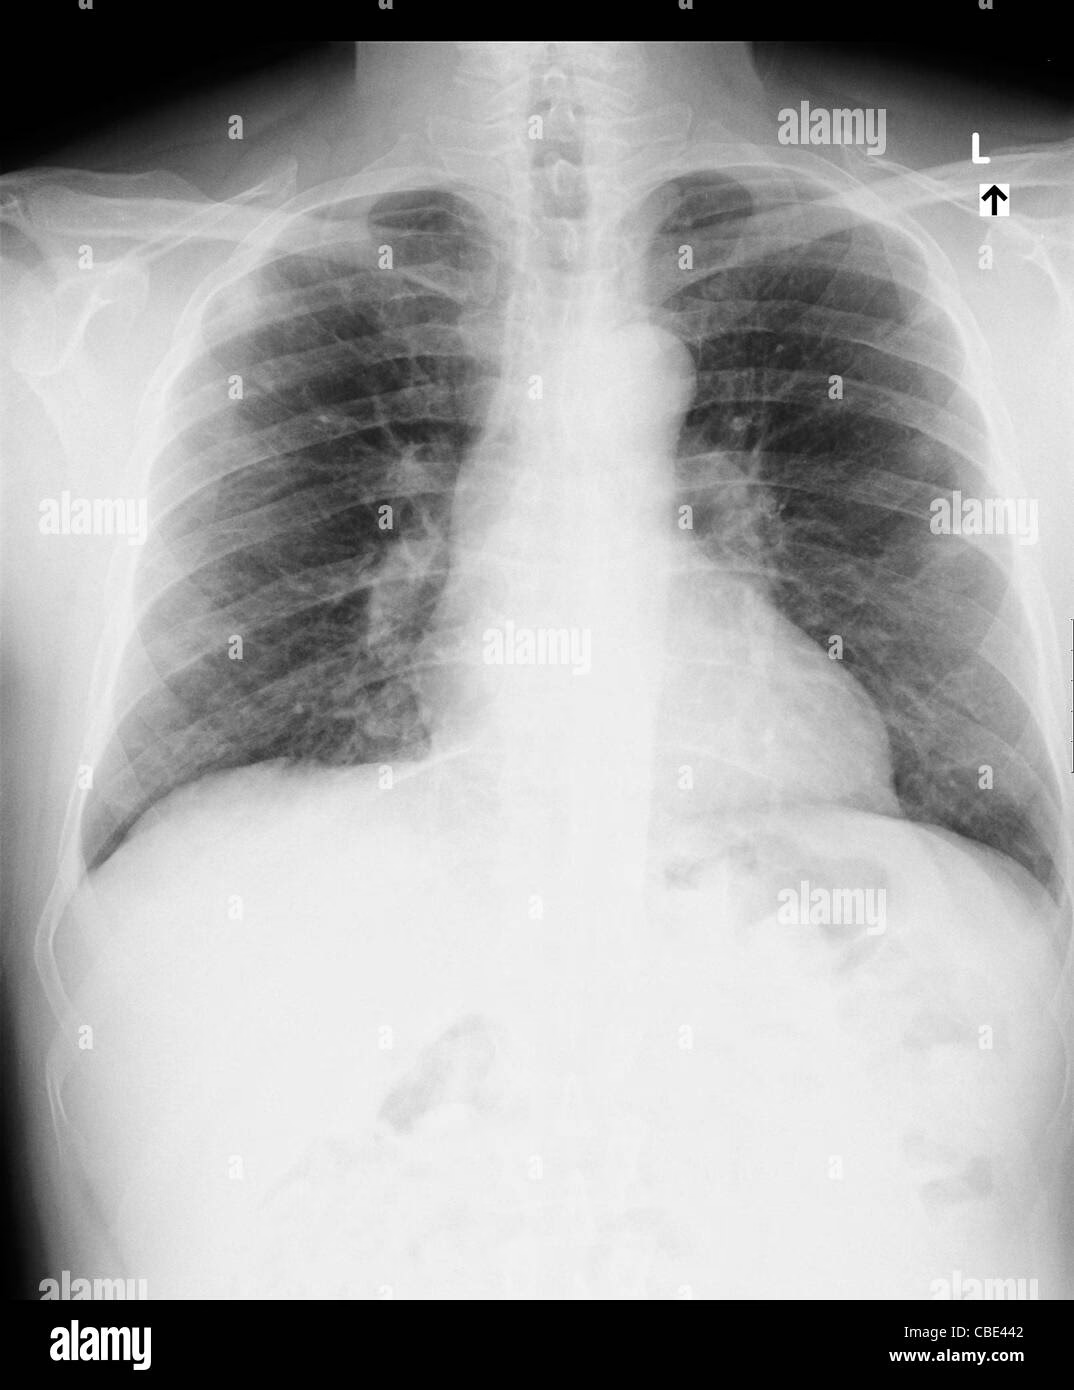

Et røntgenbillede giver lægen et vindue ind til din brystkasse. På et billede af sunde lunger vil lungefelterne fremstå mørke, næsten sorte, hvilket indikerer, at de er fyldt med luft. Hjerteskyggen vil have en normal størrelse og form, og mellemgulvet vil have en glat, buet kontur. Knoglerne, som ribbenene, vil fremstå hvide og skarpe.

Ved lungebetændelse vil et røntgenbillede ofte vise tætte, hvide eller tågede områder i en eller begge lunger. Disse områder repræsenterer pus og væske, der har fyldt de små luftsække (alveoler) som følge af en infektion.

Akut bronkitis er ofte forårsaget af en virus og vil typisk ikke vise sig på et røntgenbillede. Lægen kan dog bestille et for at udelukke lungebetændelse, hvis symptomerne er alvorlige eller langvarige.

Hos nogle patienter med vedvarende vejrtrækningsproblemer efter en COVID-19-infektion kan et røntgenbillede afsløre vedvarende tågede områder eller tegn på ardannelse (fibrose) i lungerne.

| Astma | Normalt billede. Kan vise tegn på hyperinflation i alvorlige tilfælde. | Diagnosen stilles primært via lungefunktionstest (spirometri). |